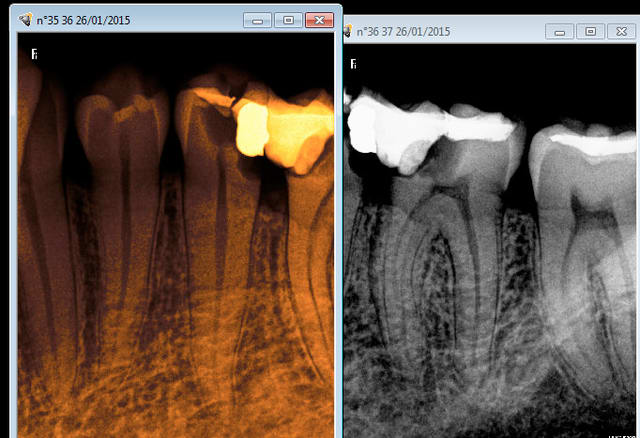

Mais apparemment le protocole a été le meme en endo. Et sur la 15 d'ailleurs ca chie pas un peu à l'apex ?